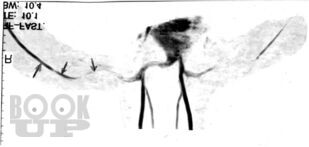

В руководстве обобщен практический опыт и анализ современной литературы по диагностике и лечению 30 редких или атипично протекающих неврологических синдромов и болезней. Обсуждаются аспекты этиопатогенеза, клинической картины, дифференциальной диагностики, наиболее типичные тактические и терапевтические ошибки.